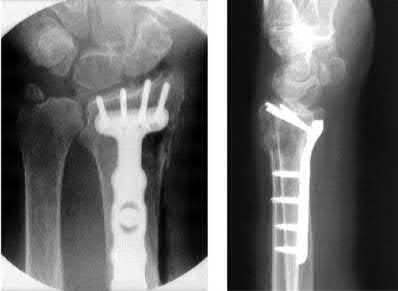

What is the most common type of malalignment after intramedullary nailing of distal 1/3 extra-articular tibia fractures using a infrapatellar approach when compared with plating?

The most common type of malalignment after intramedullary nailing of distal 1/3 extra-articular tibia fractures using an infrapatellar approach when compared with plating is valgus malalignment.

Fixation of distal one-third tibial shaft fractures can be successfully treated with either intramedullary nailing or plating. The literature describes advantages and disadvantages to both approaches, however intramedullary nailing has been shown to lead to increased rates of valgus malunion. Recent studies have shown that using a suprapatellar approach may decrease the incidence of valgus malalignement.

Vallier et al performed a randomized prospective study to compare plate and nail stabilization for distal tibia shaft fractures by assessing complications and secondary procedures. One-hundred and four patients were randomized to either reamed intramedullary nailing, or medial distal tibia plate fixation.

Primary angular malalignment was identified in 17 patients (16.3%). This included four patients treated with tibial plating (8.3%) and 13 patients treated with nails (23%, P = 0.02). Eight of these (7.7% of all patients) had malalignment between 6° and 10° of angulation. Valgus was the most common

angular deformity, accounting for 70% of angular deformity cases.

Avilucea et al. looked at the immediate postoperative alignment of distal tibia fractures (within 5 cm of the tibial plafond) treated with suprapatellar intramedullary nail (IMN) insertion compared with the infrapatellar technique. They found primary angular malalignment of ≥5 degrees occurred in 35 (26.1%) patients with infrapatellar IMN insertion and in 5 (3.8%) patients who underwent suprapatellar IMN insertion. They conclude suprapatellar IMN technique results in a significantly lower rate of malalignment compared with the infrapatellar IMN technique.